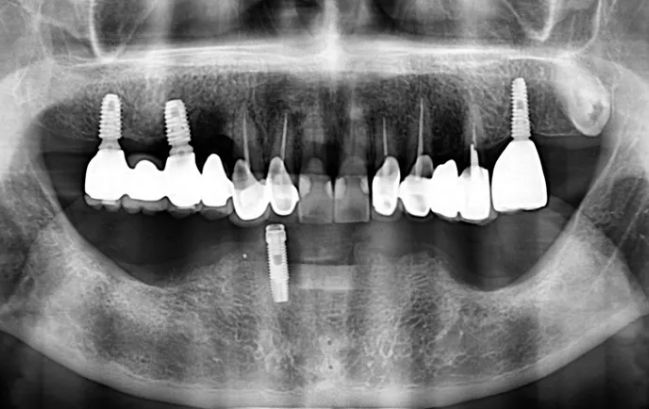

50대 남성, 원데이 수면 전체 임플란트 9개 식립